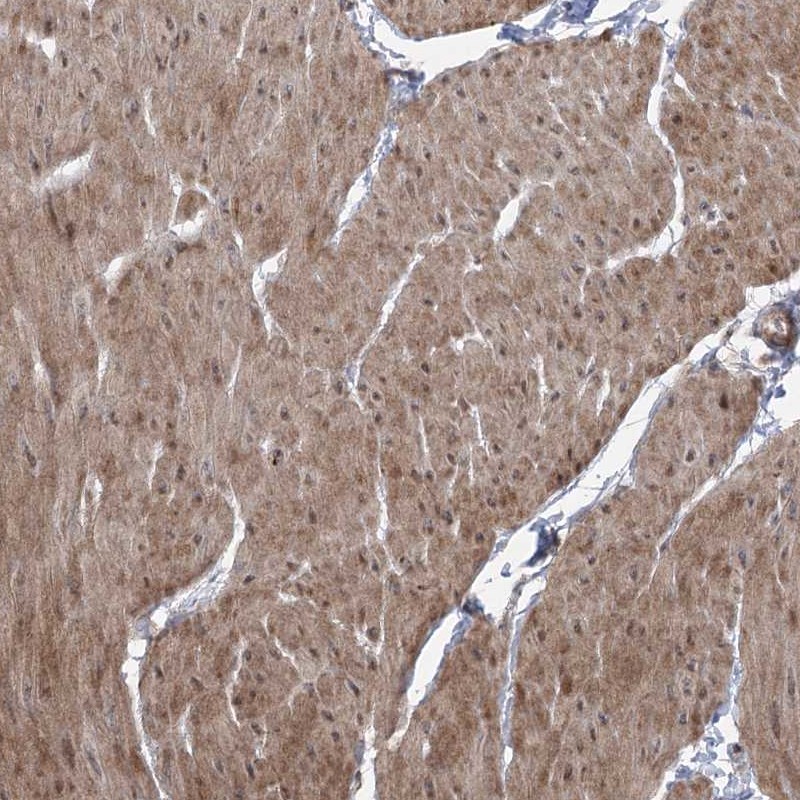

Immunohistochemical staining of human smooth muscle shows cytoplasmic positivity in smooth muscle cells.